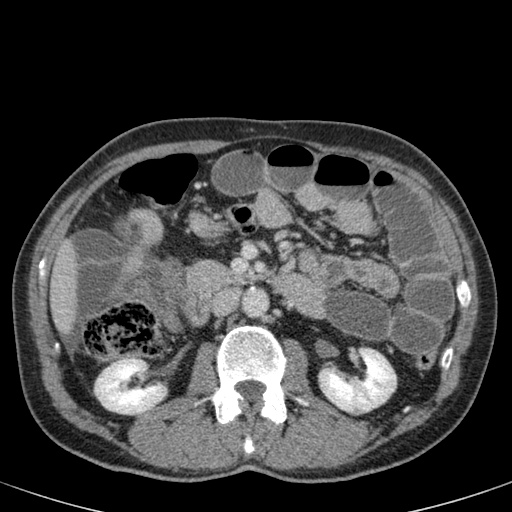

Đây là một bệnh nhân bị tắc ruột non.

Cuộn qua các hình ảnh.

Bạn có thể tìm thấy quai kín và nguyên nhân gây ra nó không?

Khi tiếp nhận bệnh nhân tại phòng cấp cứu với biểu hiện nghi ngờ tắc ruột non (SBO), điều quan trọng nhất chúng ta cần làm, ngoài việc chẩn đoán xác định, là xác định sự hiện diện hay vắng mặt của tình trạng thắt nghẹt.

CT là phương pháp chẩn đoán hình ảnh được lựa chọn trong đánh giá bệnh nhân nghi ngờ tắc ruột non.

Hình ảnh CT của tắc ruột non dạng quai kín phụ thuộc vào hai yếu tố:

- chiều dài đoạn ruột tạo thành quai kín

- hướng của quai ruột so với mặt phẳng tạo ảnh

Nếu quai kín ngắn và nằm trong mặt phẳng tạo ảnh, chúng ta sẽ thấy quai ruột hình chữ U hoặc chữ C.